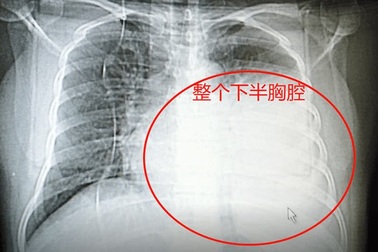

Ho khan lâu ngày, cô giáo giật mình phát hiện ung thưBản thân là giáo viên, cô Ngô nghĩ tình trạng ho khan lâu ngày bắt nguồn từ việc nói nhiều. Có nằm mơ cô cũng không nghĩ cơ thể có khối u to như trái dưa hấu chèn ép tim.